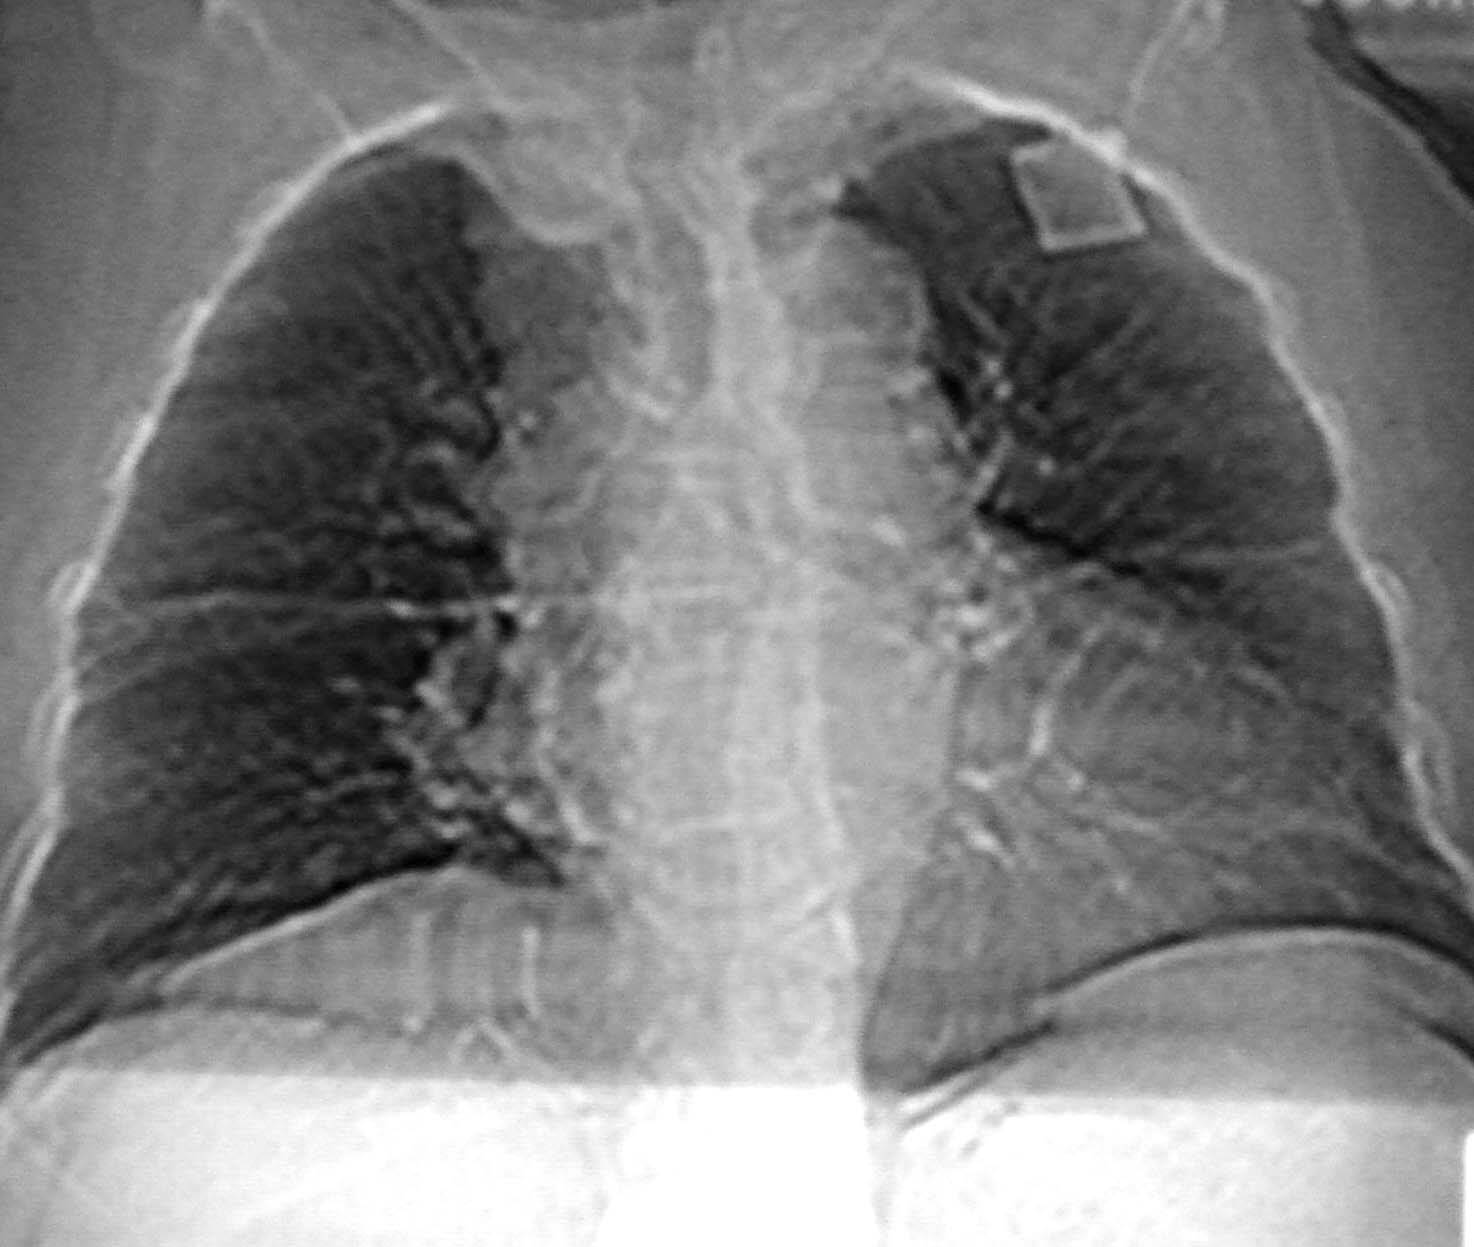

女78岁咳嗽咳痰无咳血平片报右上肺不张、慢支、肺气肿、请老师们帮忙看看,箭头所指是什么?是占位吗?有肺气肿吗?谢谢

箭头所指考虑血管影;纵隔内及双肺门区多发淋巴结钙化;不支持肺气肿。

箭头所指考虑血管影(头臂血管);纵隔内及双肺门区多发淋巴结钙化;不支持肺气肿。